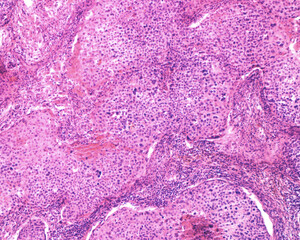

Human ovary carcinoma..

Human ovary carcinoma